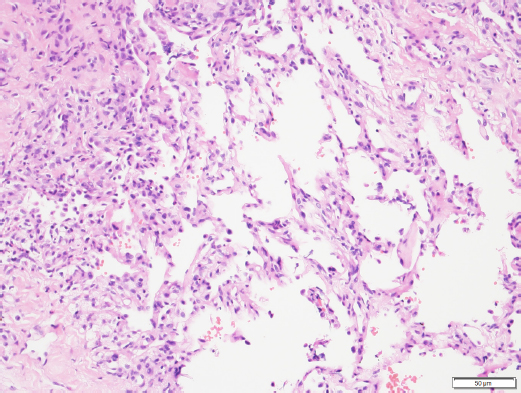

Histopathologic results of the sample confirmed marked, multifocal, chronic, neutrophilic, and eosinophilic granulomatosis with a fibrous capsule (Figs. 4 and 5).

Fig. 4. Histopathology of the pulmonary mass via a Trucut biopsy. Overview revealing fibrosis and an eosinophilic multifocal inflammatory component (40× magnification). Image courtesy of Dr. May TSE from CityU VDL, Hong Kong.

Fig. 5. Histopathology of the pulmonary mass. Fibrosis, eosinophilic multifocal inflammation and alveolar septa (200× oil magnification). Image courtesy of Dr. May TSE from CityU VDL, Hong Kong.